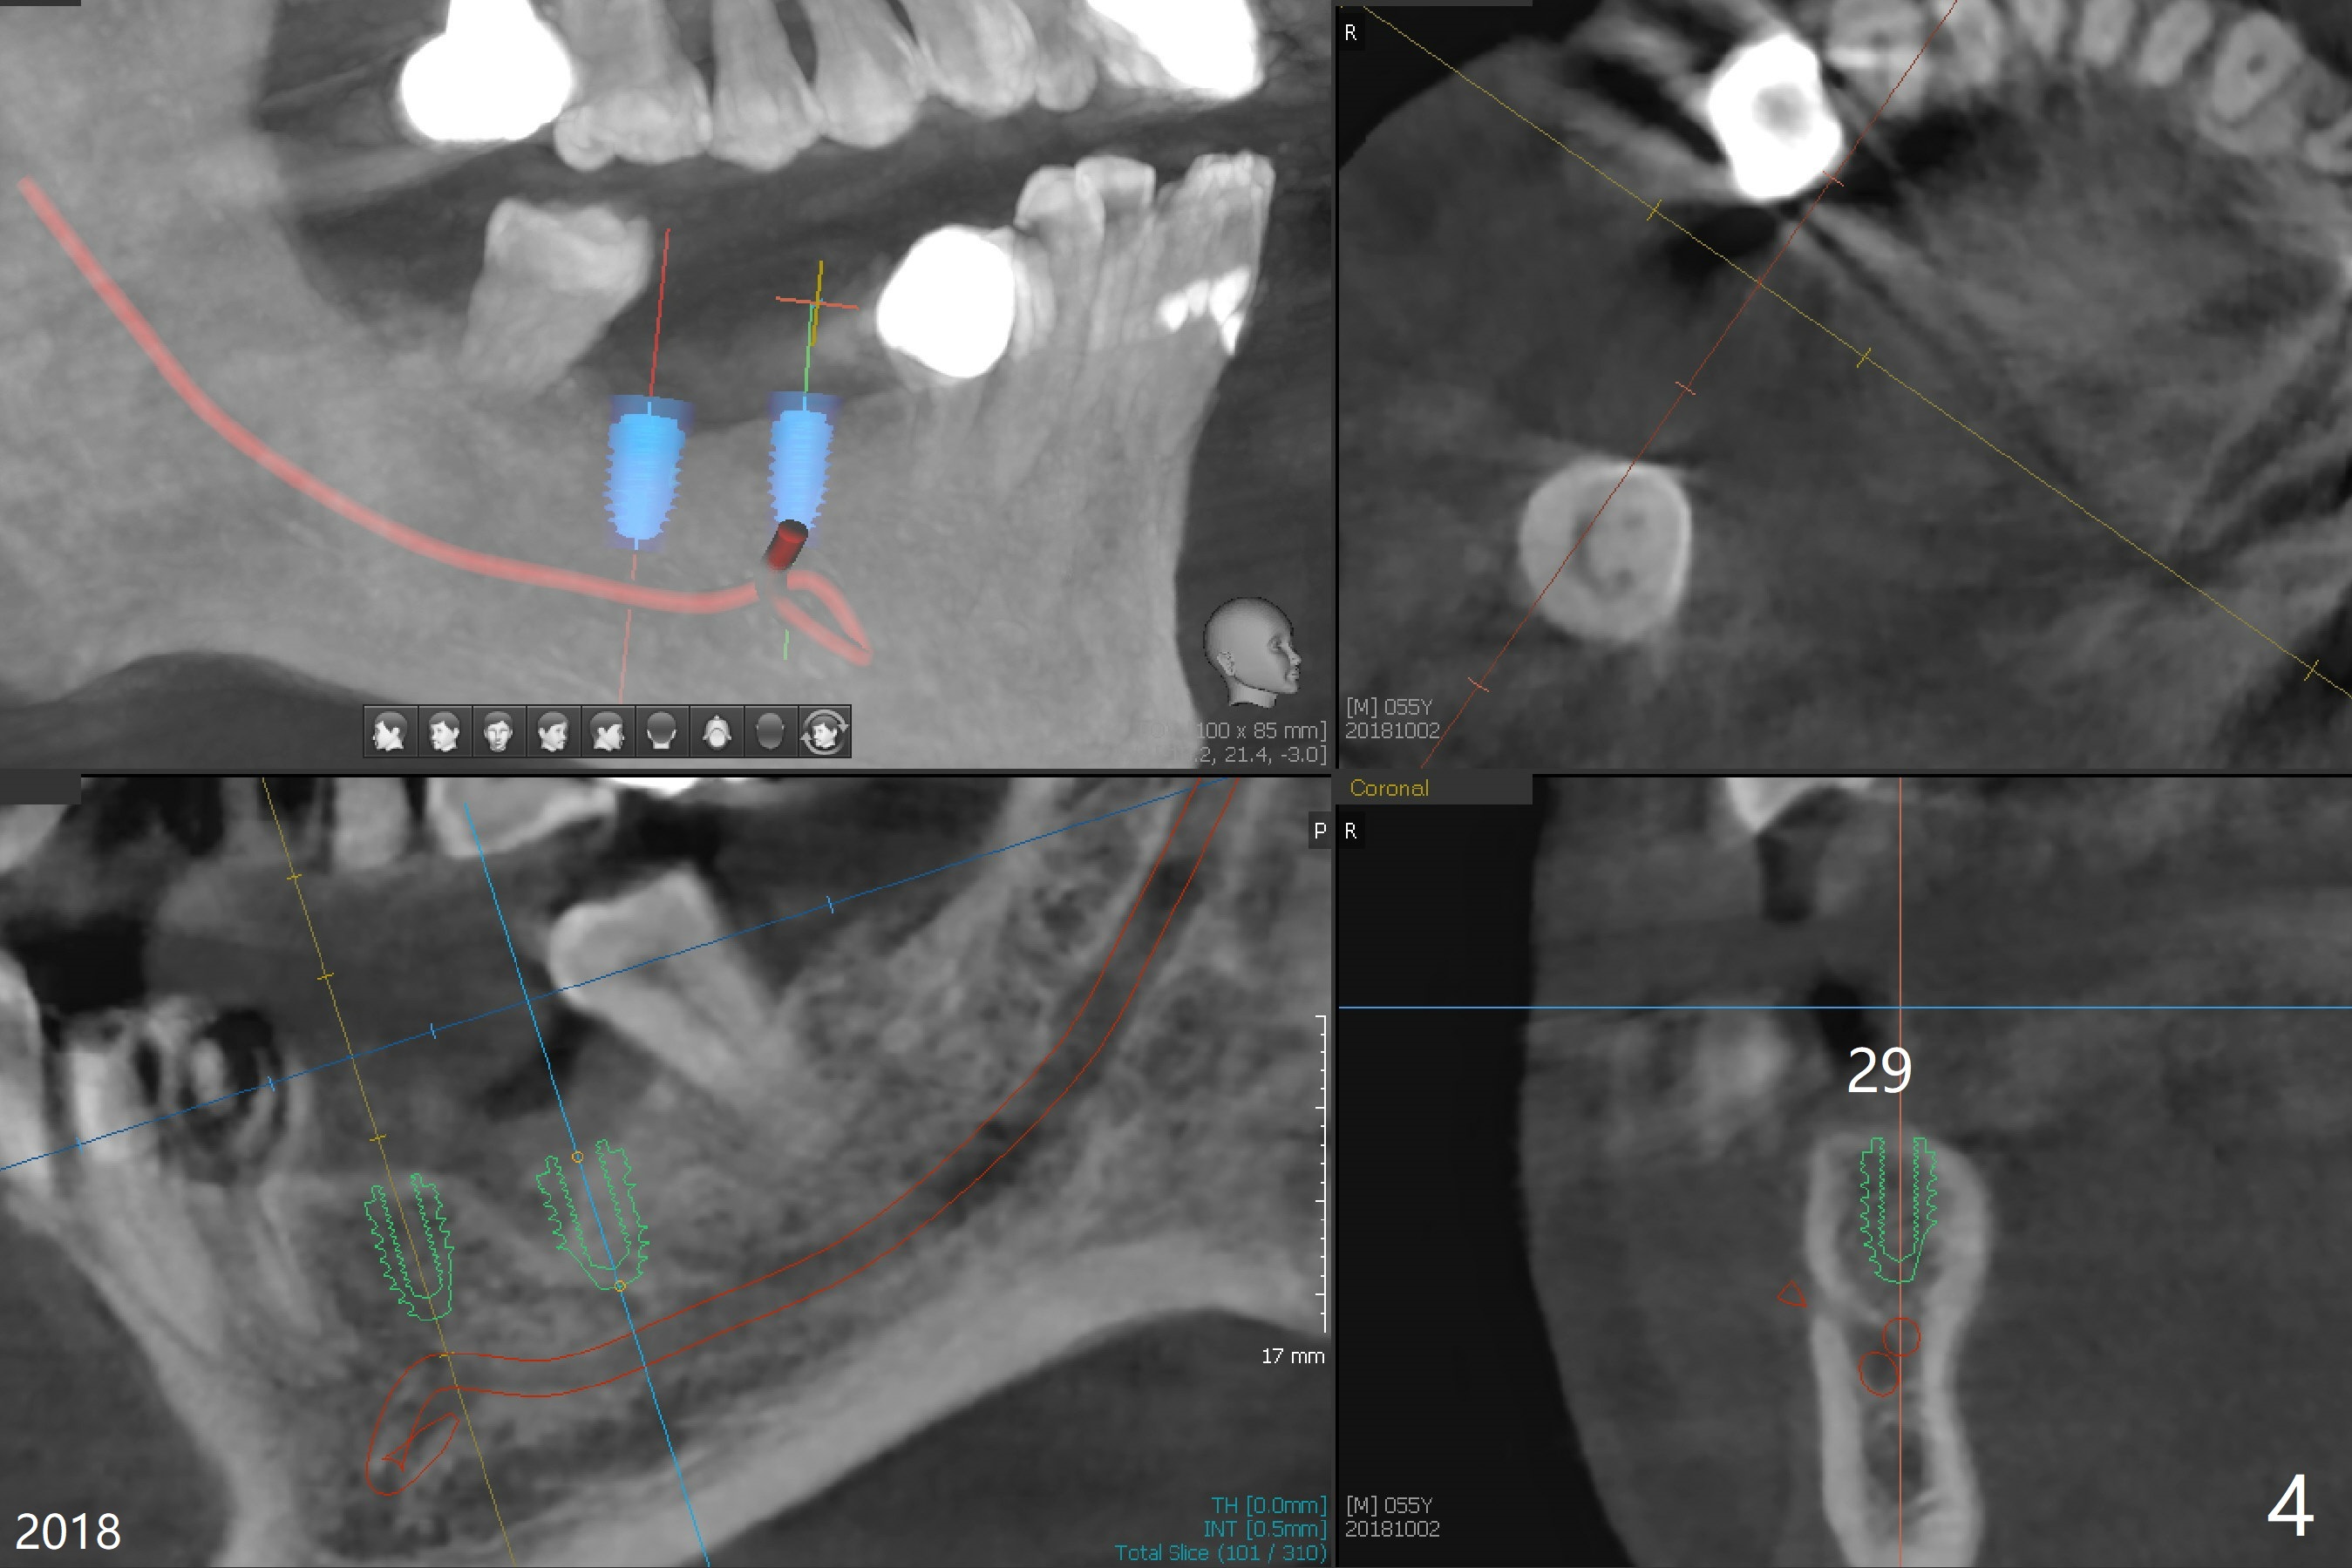

A 55-year-old man had #30 extracted and #29 pontic removed ~ 3 months ago (Fig.1,2). Short implants are to be placed (4.5x8.5 and 5x7.3 mm) with guide. Pay attention to the submandibular fossa (Fig.2 *) as related to the site of #30. New CT (Fig.3,4 (2018)) shows that implants will be 4x7.3 and 5x7.3 mm.